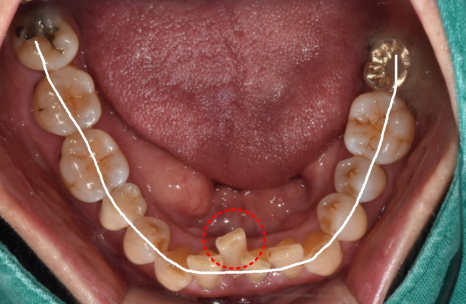

발치보다는

살릴 방법부터 고민합니다.

'자연치아 지키기'에 진심인 저는

이번 환자분의 진단 결과 앞에서

고민이 참 많았습니다.

가운데 2개는 발치가 불가피했지만,

양옆 치아들은 제법 든든하게

제자리를 지키고 있었기 때문입니다.

230602

다만 전체적으로 낮아진 잇몸뼈가

마음에 걸려,

환자분께 두 가지 선택지를

상세히 설명해 드렸습니다.

자연치아를 최대한 살릴 수 있지만

남은 치아에 무리가 갈 수 있는 '브릿지'와,

아쉽지만 옆 치아까지 정리해

염증의 원인을 근본적으로 해결하는

'임플란트'였습니다.